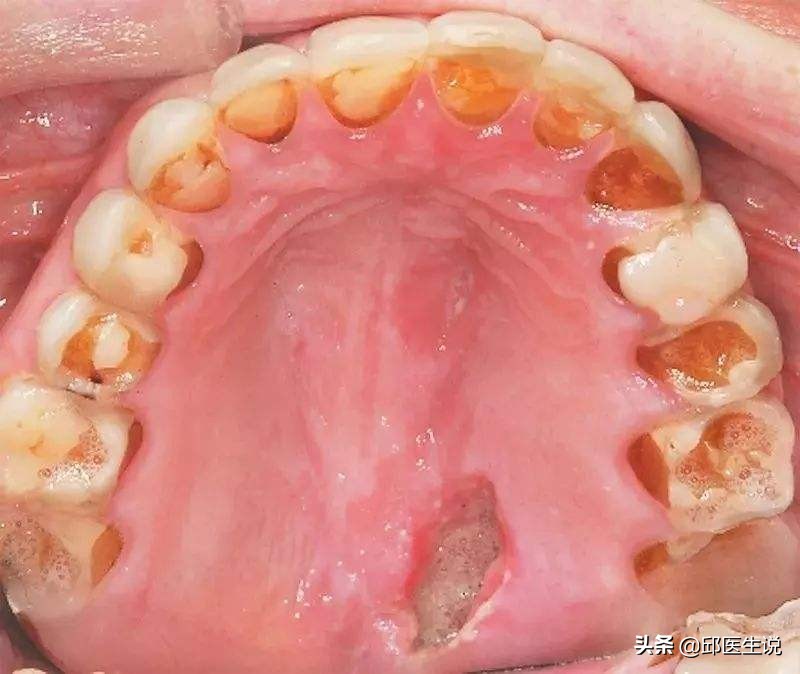

(4)破喉烂牙

胃酸的腐蚀性较强,催吐时,食物和胃酸沿着食道和口腔流出,反复腐蚀经过之处。

就连牙齿,作为人体最坚固的部位之一,都不能幸免。

若长期催吐,牙齿被胃酸反复腐蚀,就会造成不可修复的严重牙齿损伤,而且就算催吐后刷牙也无济于事。另外胃酸和扣喉都会伤害到喉咙,经常催吐的人常常会觉得喉咙疼痛无力,声音嘶哑,若是被指甲刮损出现创面,极易感染。